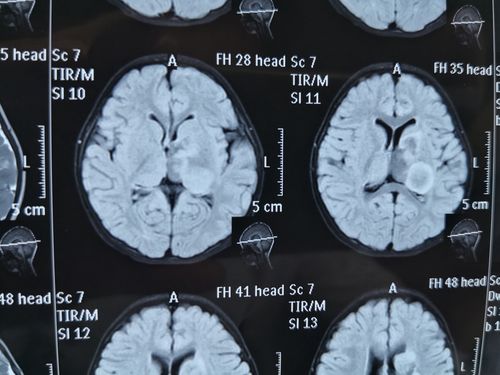

朱育霆 2岁 左侧脑室及丘脑占位 13903809976(副本)

侧脑室占位一例

侧脑室ct

侧脑室ct图片